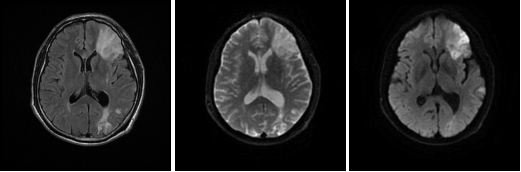

患者術(shù)后復(fù)查腦血管灌注一站式檢查, 腦血管CTA顯示原閉塞的左側(cè)大 腦 中 動(dòng) 脈M 1段 此 次 顯 影 通 暢 , 局 部 中 度 狹 窄 。 腦 灌 注 分 析 顯 示 左 側(cè) 額 葉 及 頂 枕 葉 軟 化 灶 改 變 , 基 本 同 前 ; 原 左 側(cè) 的 大 腦 中 動(dòng) 脈 供 血 區(qū) 大 面 積 灌 注 異 常 較 前 明 顯 改 善 。2 0 1 8 - 1和 2018 - 5月兩次復(fù)查, 都顯示原堵塞血管通暢, 與溶栓后對(duì)比無(wú)明顯變化。